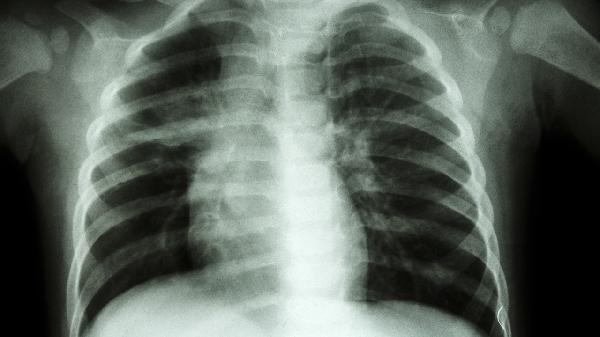

成人鸡胸病治疗期间应保持标准体重,肥胖会加重胸廓负担。睡眠时建议仰卧位并使用低枕,避免侧卧压迫胸廓。定期进行肺功能检查评估治疗效果,术后患者需每年复查胸片观察骨骼愈合情况。注意预防呼吸道感染,咳嗽时可用手轻压胸骨减轻震动疼痛。